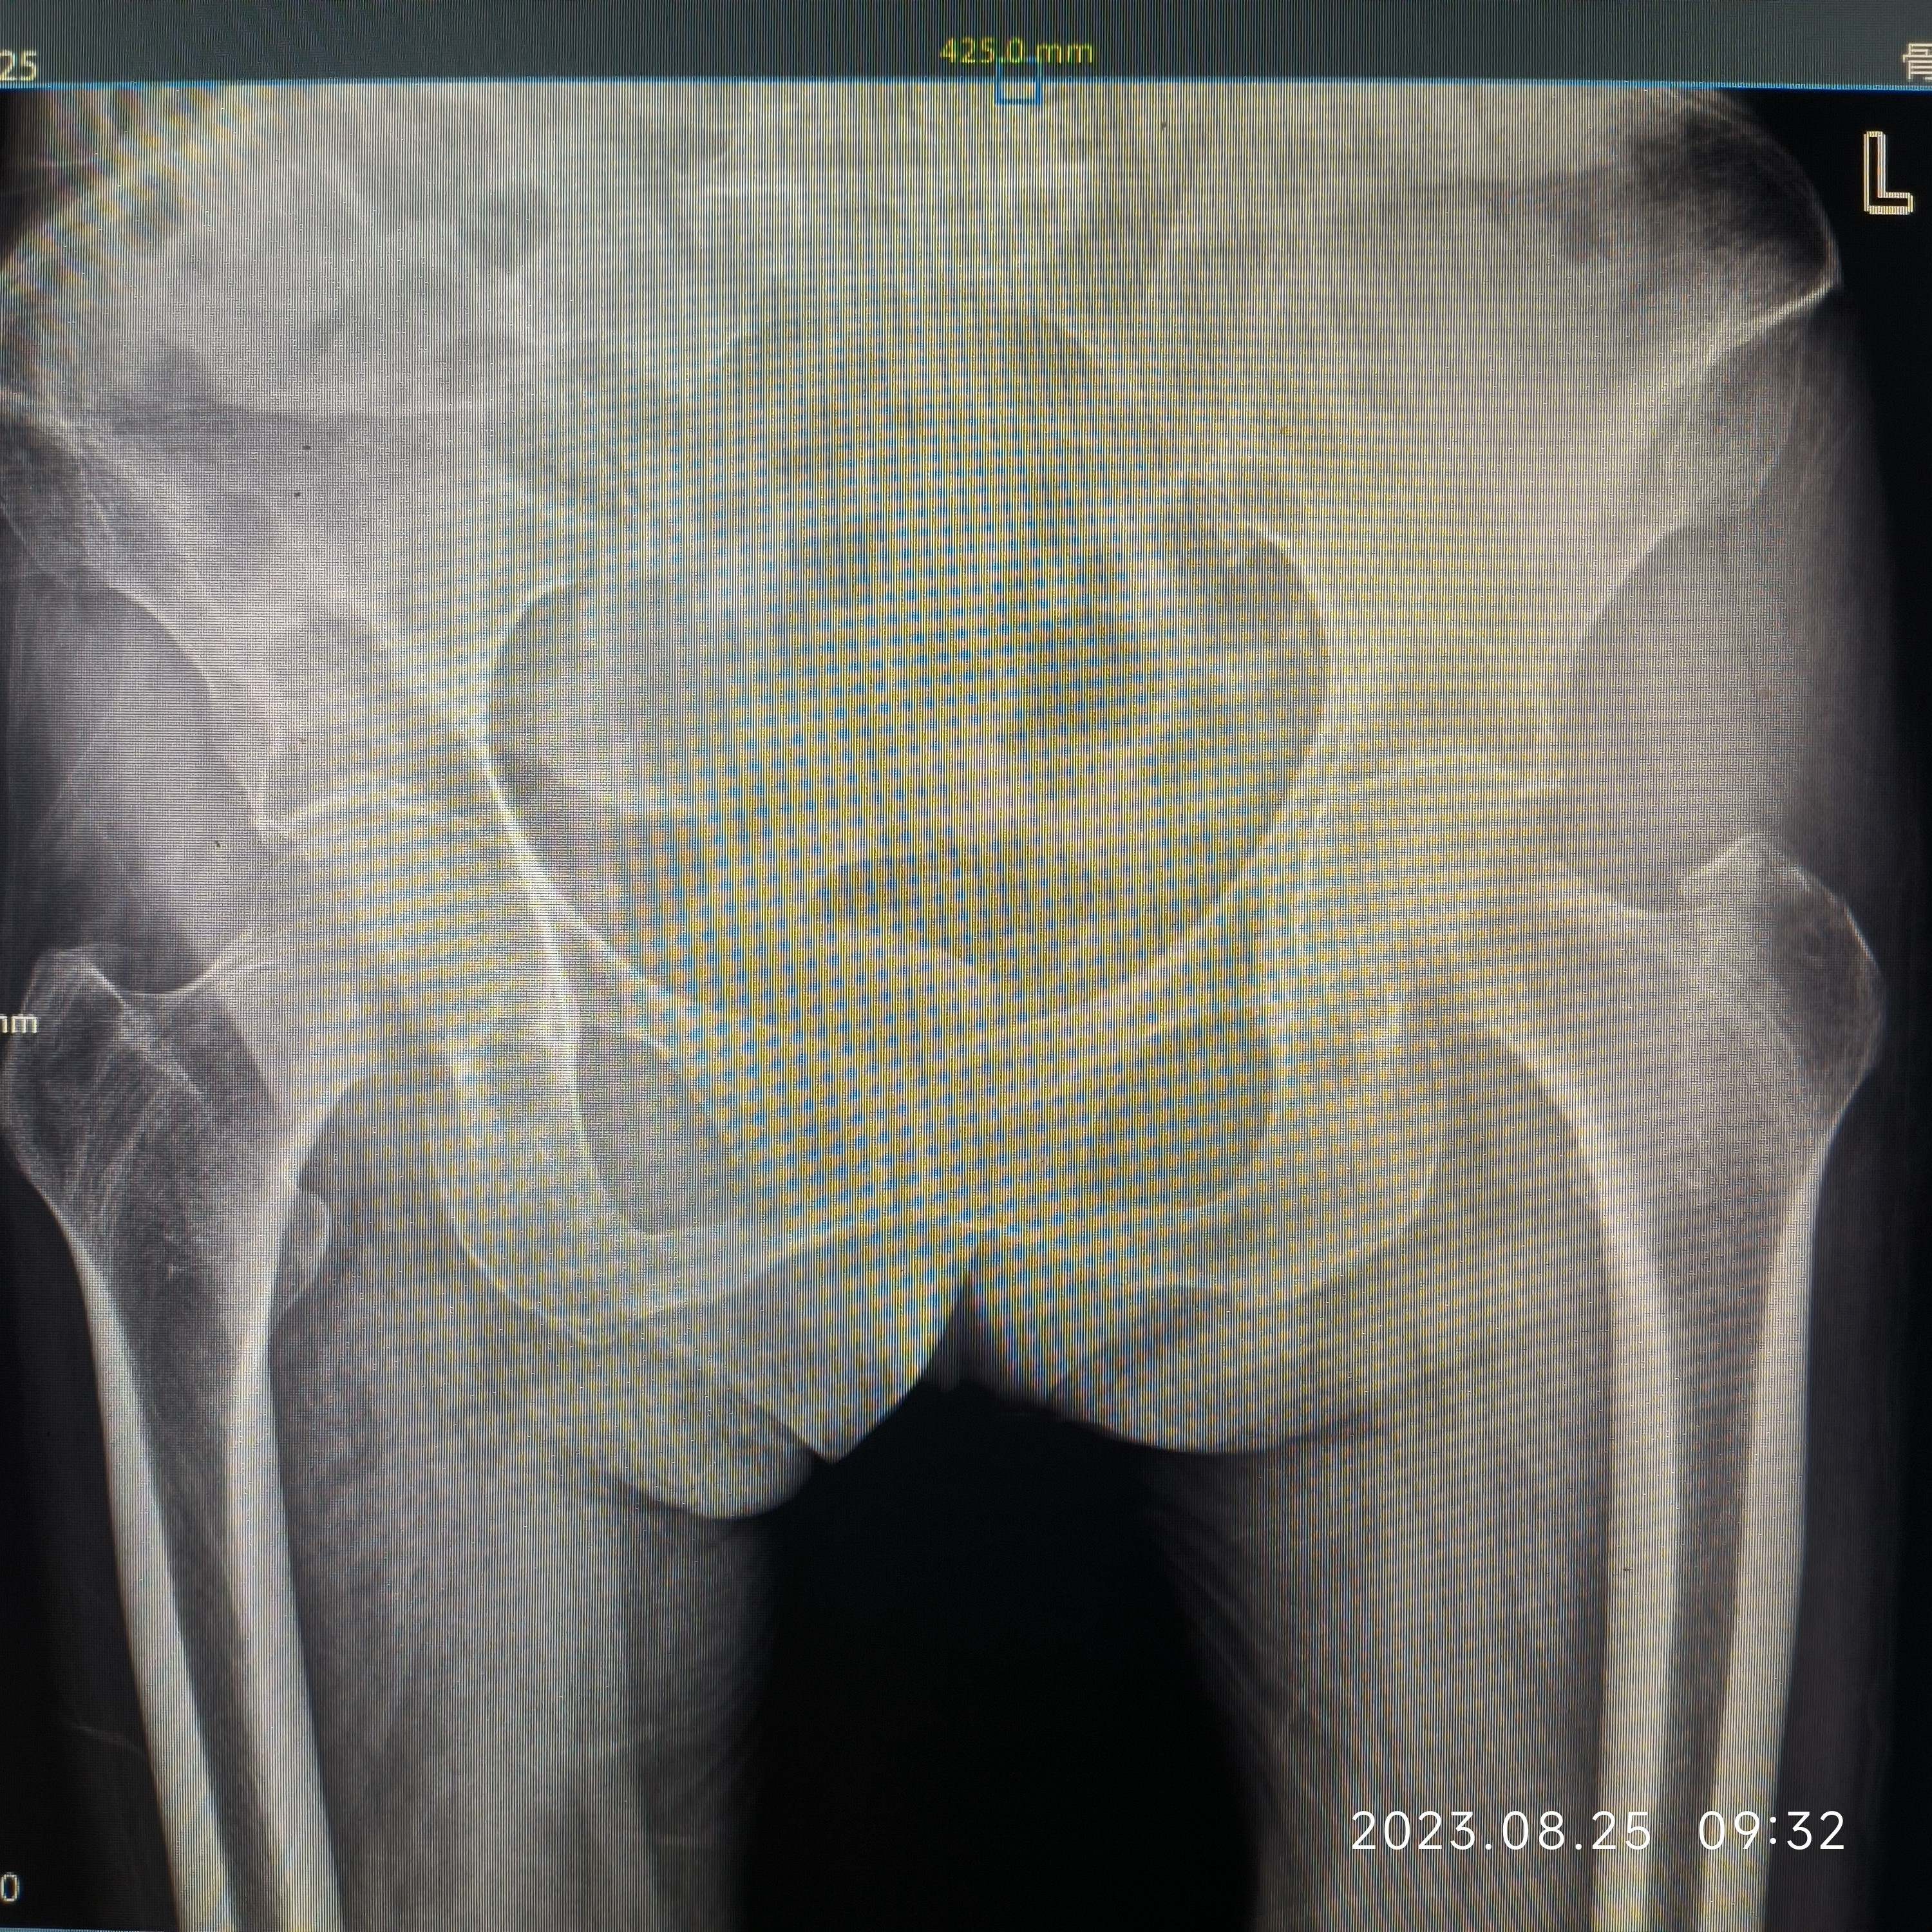

女,80岁,左股骨转子间骨折PFNa。病人营养状况一直不好,胃肠道接受能力非常差,稍微进食油腻基本上一天在10次左右腹泻(常备蒙脱石散、诺氟沙星…),家里老伴身体不好,子女忙都没法在家照顾,强烈要求手术,术前病人血色素6.5g,凝血正常,术中出血700ml左右,低血压报警一次,用了多巴胺后高压维持80mmHg左右,术后输了2U红悬+400ml血浆,第一天复查血色素5.9g,第二天复查血色素6.0g,术后1周复查血色素6.2g……病人精神状态一直还可以……